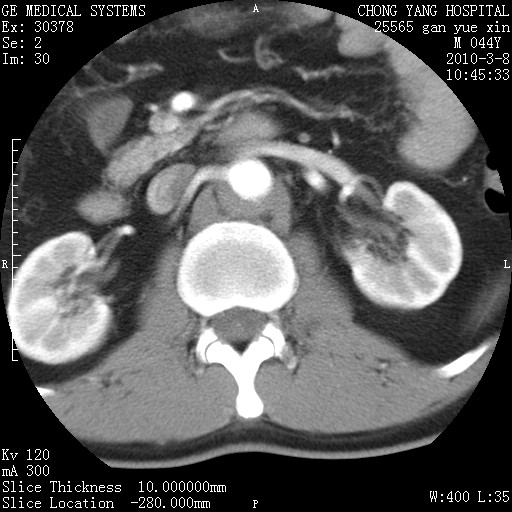

标题: CT24940:主动脉增强,典型病例。 [打印本页]

标题: CT24940:主动脉增强,典型病例。

夹层动脉瘤。

动脉夹层

夹层动脉瘤,典型

主动脉夹层。

动脉夹层的分型:

⒈debakey分型:根据主动脉夹层累及部位,分为三型:ⅰ型:原发破口位于升主动脉或主动脉弓部,夹层累及升主动脉、主动脉弓部、胸主动脉、腹主动脉大部或全部,少数可累及髂动脉。ⅱ型:原发破口位于升主动脉,夹层累及升主动脉,少数可累及部分主动脉弓。ⅲ型:原发破口位于左锁骨下动脉开口远端,根据夹层累及范围又分为ⅲa,ⅲb。ⅲa型:夹层累及胸主动脉。ⅲb型:夹层累及升主动脉、腹主动脉大部或全部。少数可累及髂动脉。

⒉stanford分型:a型:夹层累及升主动脉,无论远端范围如何。b型:夹层累及左锁骨下动脉开口以远的降主动脉。

夹层动脉瘤,少量胸水

夹层动脉瘤;左侧少量胸腔积液。

典型主动脉夹层。